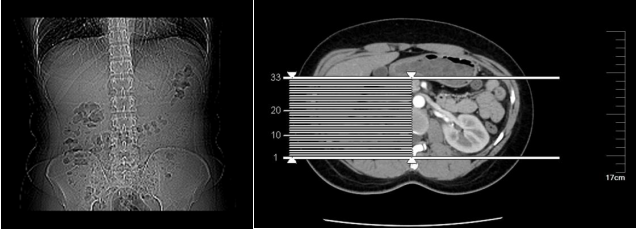

图12 详细的病理组织图(2)肾上腺CT检查,如图13-14。

图13 肾上腺CT报告

图14 肾上腺CT图案例分析嗜铬细胞瘤是一种少见的内分泌疾病,临床表现多样,且疾病演变较快有些患者可以完全没有症状,有症状的话最典型的是高血压,发作时最常见的三联征头痛、心悸、多汗症状就如这案例中的患者是在日常健康体检中发现的嗜铬细胞瘤,且血压都升高4年多,知道后却不管不问,也很容易出现问题。